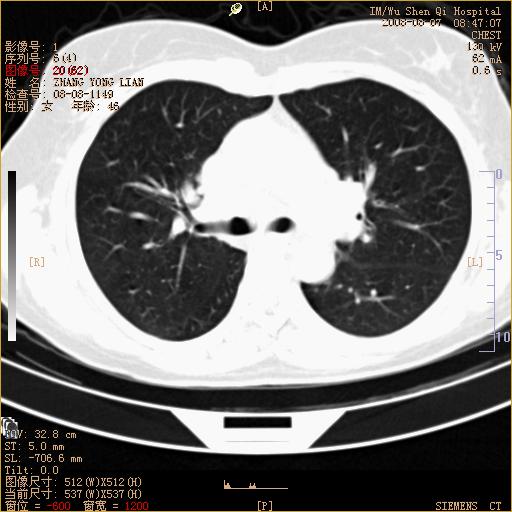

标题: CT15050:女,46岁,咳嗽胸痛一月余 [打印本页]

纵隔窗没发全,左下肺近胸膜处结节。有长毛刺,纵隔淋巴结增大,不排除恶性病变。

考虑肺癌

考虑左肺下叶后基底段周围型肺癌伴纵隔淋巴结转移可能性大。

左下肺ca并纵隔及左肺门区淋巴结转移。

1)考虑左肺下叶后基底段周围型肺癌伴纵隔淋巴结转移。2)脾内低密度灶,性质待定;不排除转移瘤可能。

考虑左肺下叶后基底段周围型肺癌伴纵隔及肺门淋巴转移。